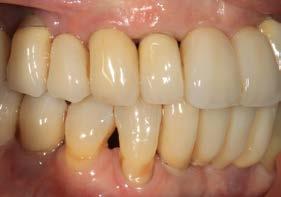

La paciente continúa bajo seguimiento periodontal. A los 5 años se observa estabilidad clínica del tratamiento (Figuras 22–24), sin recesiones gingivales ni pérdida ósea asociada en las imágenes clínicas y radiográficas.

Un año más tarde, al finalizar el periodo de seguimiento (24 años), las fotografías intraorales evidenciaron ligeras alteraciones de los tejidos blandos, con pequeñas troneras abiertas,

más evidentes en los dientes naturales conservados que en las restauraciones implantosoportadas. A pesar de estos cambios, el resultado global se consideró satisfactorio desde el punto de vista funcional y estético, especialmente en comparación con la situación clínica y radiográfica inicial previa al tratamiento (Figuras 26–31).

Figuras 26–29. Imágenes clínicas a los 25 años. Se aprecia mínima pérdida ósea en dientes e implantes, con ligera apertura de troneras. Considerando el antecedente periodontal de la paciente, estos cambios pueden considerarse compatibles con una evolución controlada bajo mantenimiento estricto.